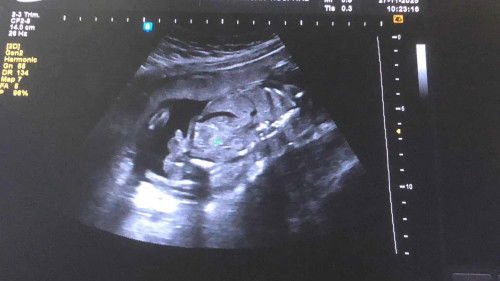

แบบนี้เรียกท้องปั้นแข็งหรือลูกโก่งตัวคะ